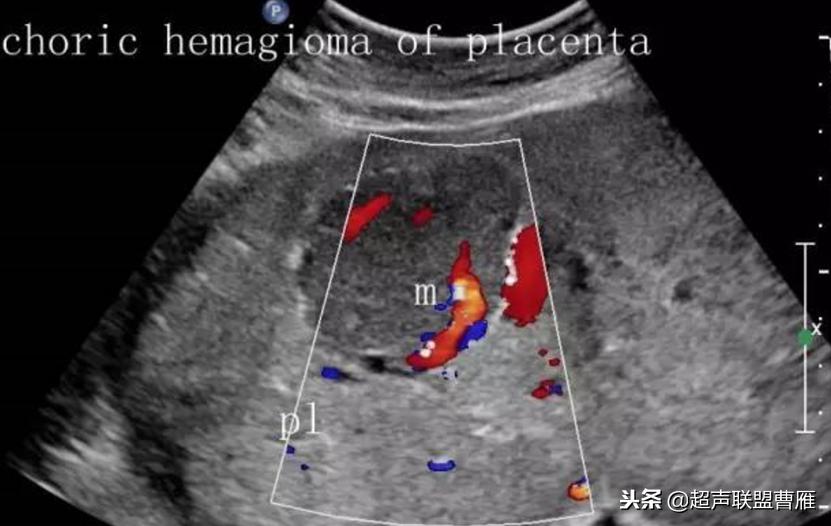

(6)彩色多普勒可以发现肿块内有血流信号

此病应与胎盘及其周边占位性声像图来鉴别,如子宫肌瘤、胎盘局部血肿等,若为子宫肌瘤,可根据两者位置不同进行鉴别,若为局部血肿者,多普勒于其内不可见血流信号显示;大的绒毛膜血管瘤可伴羊水过多,且羊水过多的程度与绒毛膜血管瘤的大小有关。